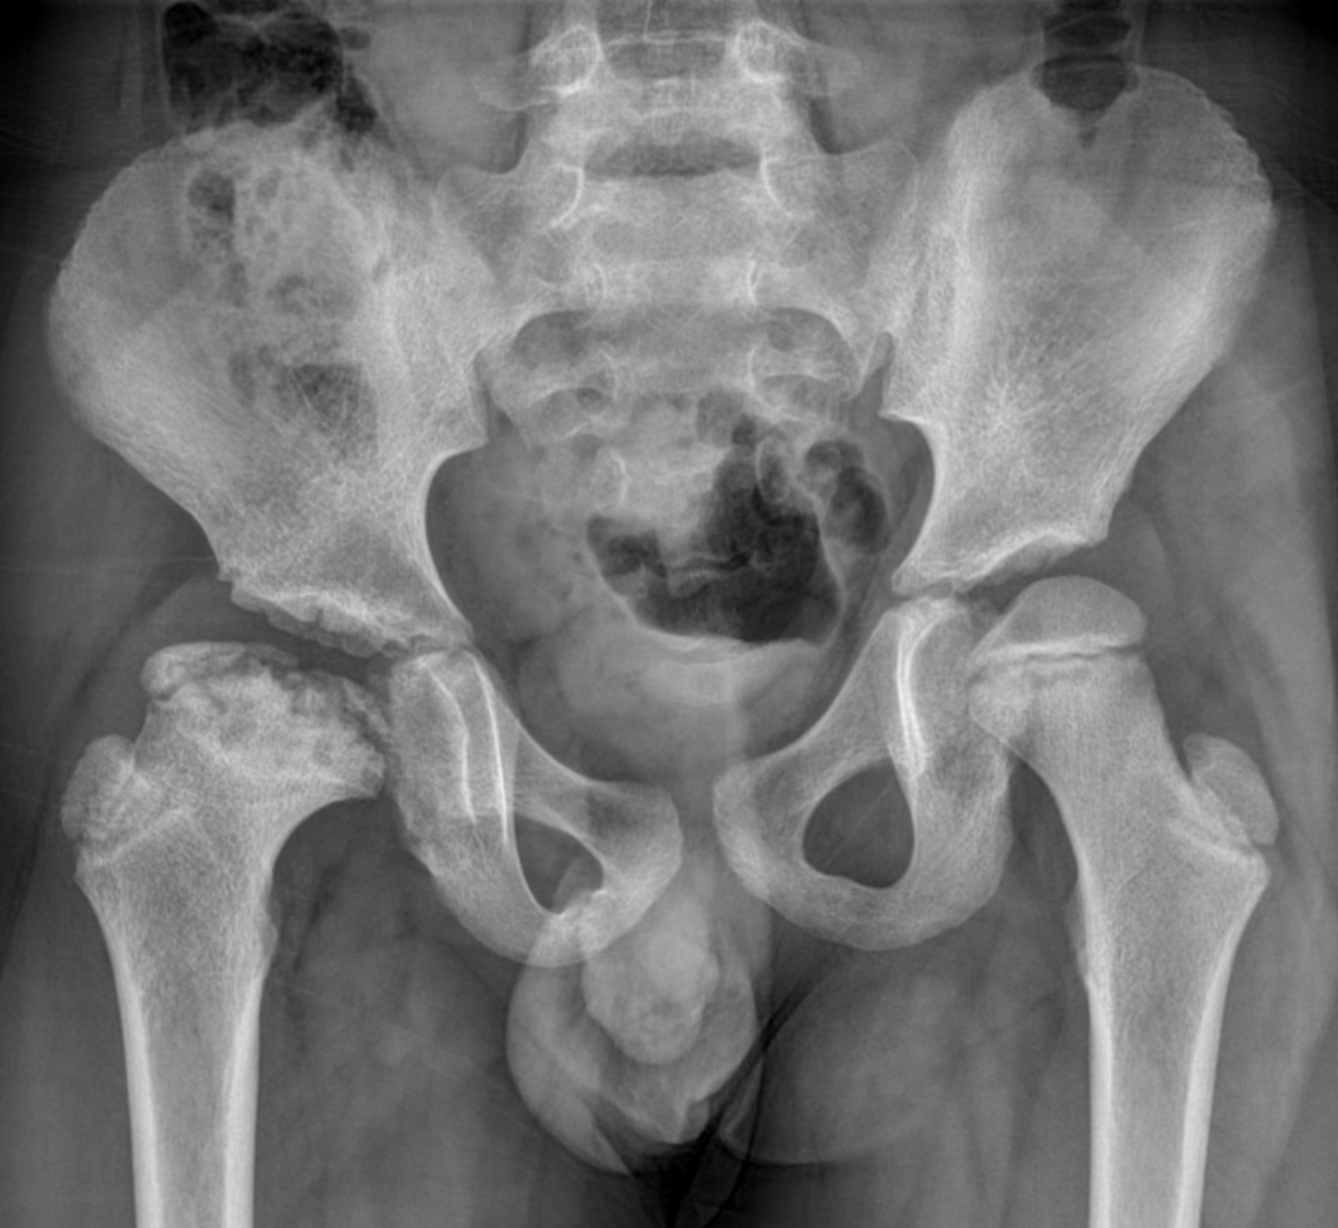

Ziekte van Legg Calvé Perthes (kinderen)

De ziekte van Legg Calvé Perthes komt vooral voor bij kinderen tussen de leeftijd van 4 en 8 jaar. Er is een verstoring van de bloedvoorziening van de heupkop. Hierdoor gaat het bot zwakker worden en kan dit gedeeltelijk of volledig inzakken en misvormen. Naargelang de uitgebreidheid van de aantasting van de kop onderscheidt men verschillende graden. Over verloop van tijd gaat de bloedvoorziening van de kop zich herstellen. Het ingezakte bot kan zich dan terug modelleren waarbij er dan meestal een verbreding en afplatting van de heupkop optreedt. De behandeling is meestal gebaseerd op een afwachtende houding en steunverbod. Zelden is chirurgie noodzakelijk.